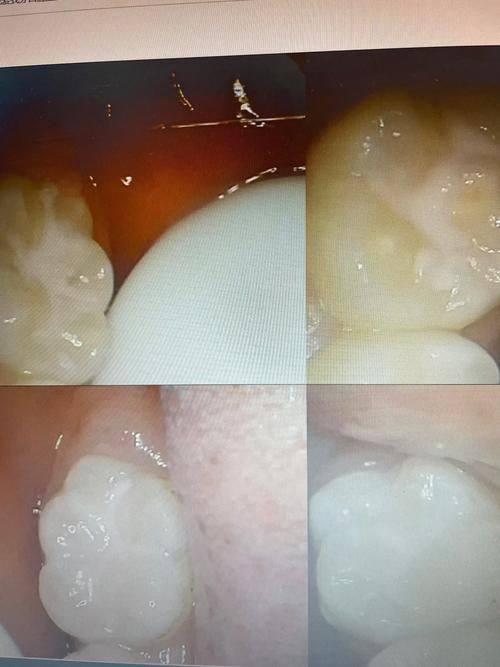

3. 口腔疾病治疗:对于牙痛、牙周病、龋齿等常见口腔疾病,医生凭借丰富的经验和专精技术,能够进行正确诊断和有效治疗。